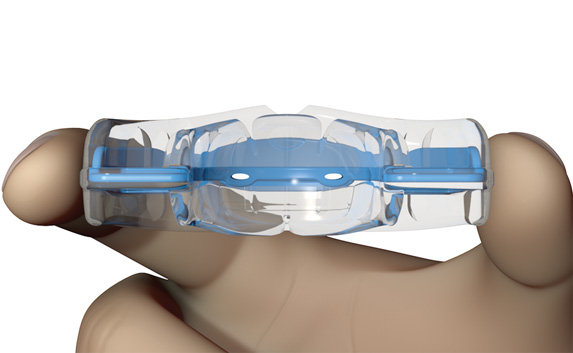

The T3 focuses on dental alignment after arch development is complete and is the only appliance in the entire Myobrace® range that is similar to an orthodontic tooth positioner. The appliance comes in seven different sizes, with the appropriate size being selected using the T3 Ruler. It has individual tooth slots, which not only align the teeth, but act as separating wedges for extra arch development and correction of mild rotations. Compliance is essential to prevent relapse in the arch form, which can happen when the T3 is not worn regularly. Move to the T4 when the T3 has aligned the teeth sufficiently.

Firmer material

imparts extra force to promote arch development.

Tooth slots

act as separating wedges to increase arch length and de-rotate teeth.

Modified Dynamicore™ (Frankel Cage)

combines with the tooth slots to optimise dental alignment.

Small breathing holes

help to establish nasal breathing.

Lip bumper

discourages overactive lip muscles during a reverse swallow.

Tongue tag

encourages correct tip of the tongue positioning.

Tongue elevator

encourages the body of the tongue to rest in the roof of the mouth.

Low sides

concentrate the appliance on dental alignment alone.